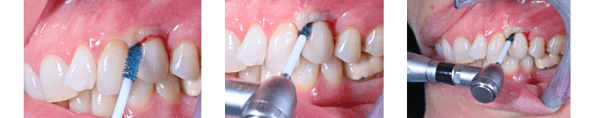

Dette webinar tar for seg vedlikeholds- og behandlingsstrategier for implantatpasienter med mucositt og peri-implantitt, med tanke på å kunne oppnå et optimalt langtidsresultat. Målet er at du som kursdeltaker skal komme tilbake til klinikken og føle deg bedre rustet til å håndtere implantatkomplikasjoner og være tryggere på hvordan du kan unngå katastrofen. Du får med deg nye verktøy i din kliniske portefølje.